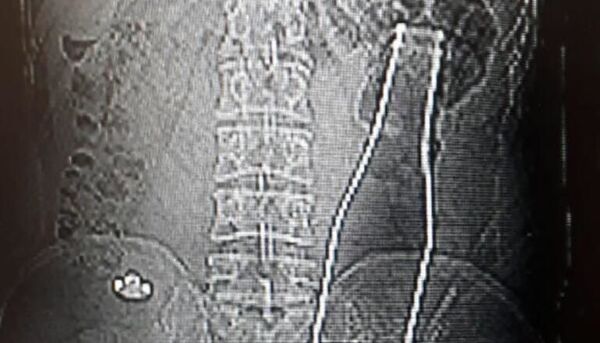

10:27 10.07.2020 (güncellendi: 10:29 10.07.2020) Beylikdüzü’nde 9 yaşındaki çocuk oyuncak olarak satılan stres bilyeleri olarak da bilinen neodyum adlı güçlü mıknatıstan 42 adet yuttu. Kusma, karın ağrısı şikayetiyle hastaneye getirilen çocuğun röntgen filmi çekilince gerçek ortaya çıktı. Ameliyata alınan çocuğun delinen bağırsağından mıknatıslar çıkarıldı.

Beylikdüzü’nde 9 yaşındaki bir çocuk ailesinin haberi olmadan neodyum adı verilen stres bilyeleri olarak da bilinen 42 adet mıknatısı yuttu. Birkaç gün sonra şiddetli karın ağrısı ve kusma şikayeti ile hastaneye gelen çocuğun röntgeni çekildi. Röntgen filminde çocuğun midesinde boncuklar halinde yabancı bir cisim tespit edildi.

Konuyla ilgili konuşan Prof. Dr. Çay, yutulan cisimlerin normalde sindirim sistemi ile çıkabileceğini ancak çoklu mıknatısların bağırsaklarda delinmeye neden olabileceğini ifade ederek, “Bizim hastamız yaklaşık 42 tane bu mıknatıstan yutmuş çeşitli hastanelere müracaat etmiş. Burada yapılan incelemelerde çekilen filmlerde tesadüfen bu mıknatısları yuttuğunu biz radyografide gördük hastamızı ameliyata aldık. İnce bağırsak uç kısmında delinme oluşturmuştu. Biz bu mıknatısları çıkardık” dedi.